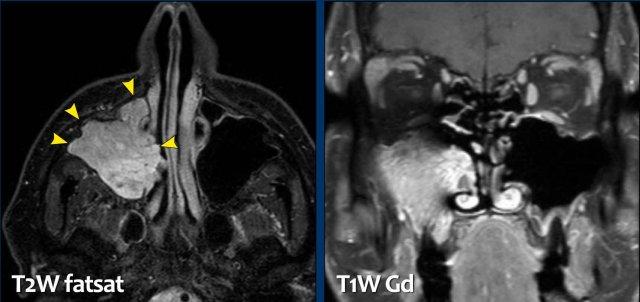

Đây là một trường hợp u nhú đảo ngược khác.

Tổn thương biểu hiện là một khối niêm mạc có bờ thùy múi với hình ảnh ‘cuộn não’.

Trông như hình ảnh các hồi não (đầu mũi tên).

Đặc điểm này có tính đặc hiệu nhất định đối với u nhú đảo ngược.